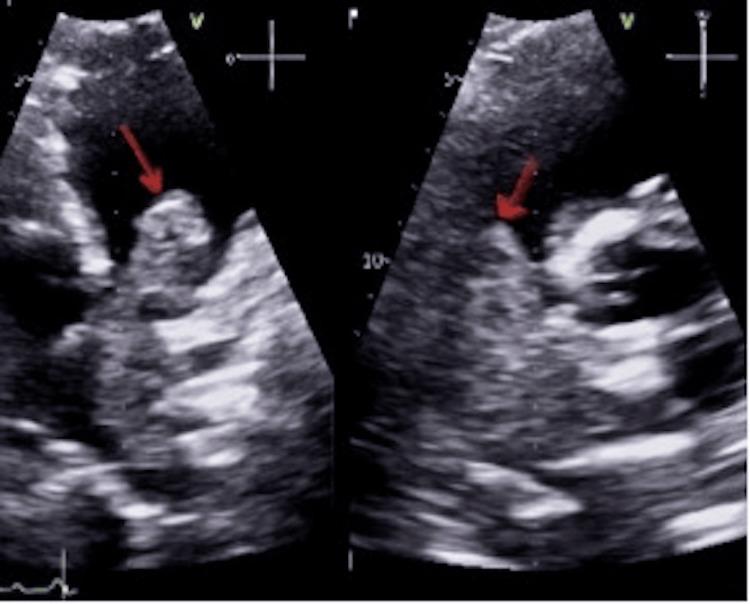

Primary pleural Ewing sarcoma is a rare type of Ewing sarcoma with only a few case reports identified in the literature. The condition is challenging to diagnose with deceiving symptoms and wide differential diagnosis. Diagnosis is confirmed with a combination of radiological and pathological assessment. Treatment is similar to other types of Ewing sarcoma with chemotherapy and surgery being the mainstay of treatment. We identify an unusual presentation of pleural Ewing sarcoma in a 31-year-old male with a mass extending into the right ventricular outlet causing rapid deterioration of the patient.

原发性胸膜尤文肉瘤是一种罕见的尤文肉瘤类型,文献中仅有少数病例报告。该疾病的症状具有欺骗性,鉴别诊断范围广泛,诊断具有挑战性。通过放射学和病理学评估相结合来确诊。治疗方法与其他类型的尤文肉瘤相似,化疗和手术是主要治疗手段。我们发现一名31岁男性胸膜尤文肉瘤的不寻常表现,其肿块延伸至右心室出口,导致患者病情迅速恶化。